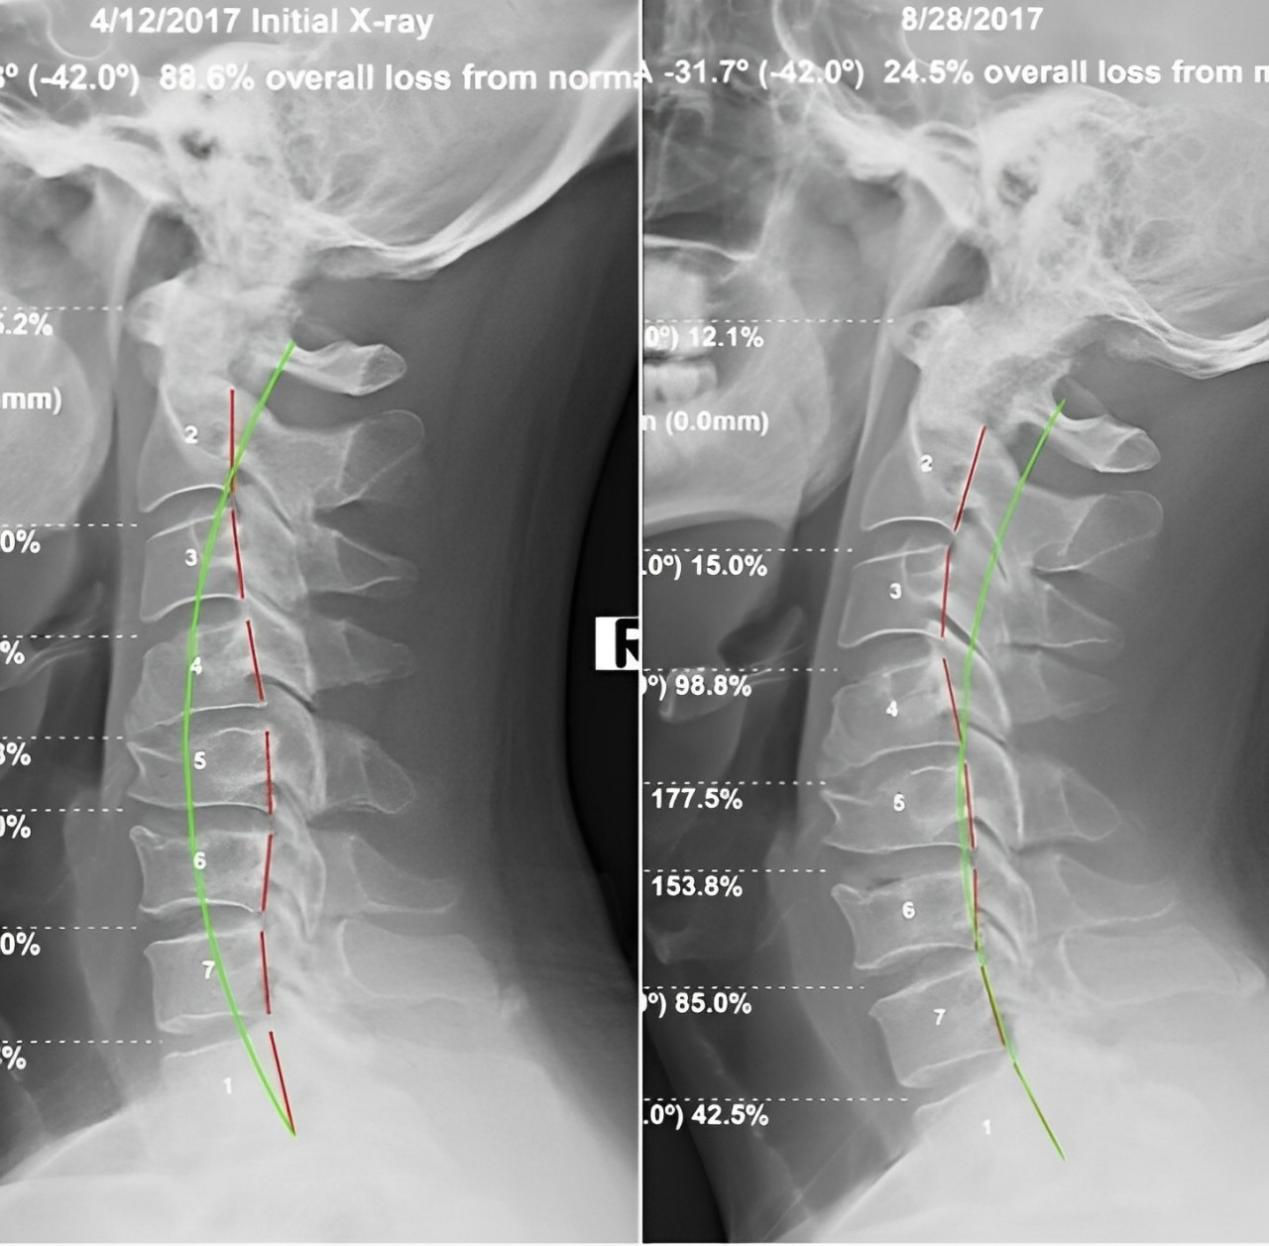

四、 恢復脊椎自然曲度

脊椎整復床的獨特設計能夠幫助恢復脊椎的自然曲度,改善脊椎側彎和不良姿勢,讓您重獲健康體態。

五、矯正完和矯正后的對比案例: